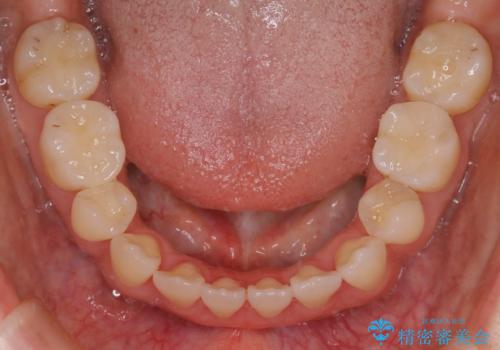

- 前歯のガタつき・噛み合わせの不調を主訴にご来院されました。

患者様のお仕事柄、目立たない装置で矯正したいとのご要望があり、今回はインビザラインを用いて抜歯矯正を行うこととなりました。

本来、抜歯によって得られる大きなスペースのコントロールはワイヤー装置の方が得意とされていますが、こちらの患者様のように犬歯が大きく手前に傾斜していて奥歯の噛み合わせにそれほど問題がないケースではマウスピース装置でも十分にコントロールできることが予測されます。